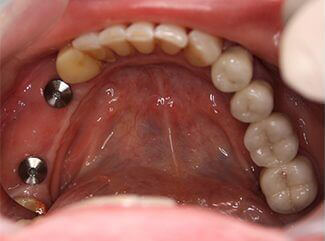

Проблема. Множественные кариозные поражения зубов, высокая степень подвижности зубов

Решение. Из-за плохого стоматологического прогноза оставшиеся зубы были удалены, а в верхнюю и нижнюю челюсти были установлены четыре зубных имплантата. На имплантаты установлены металлокерамические коронки.